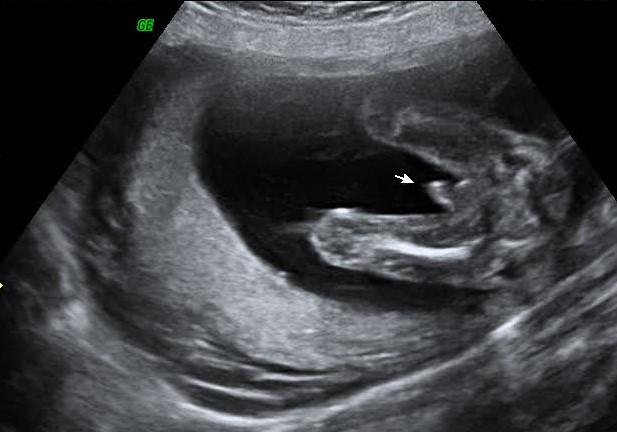

It's a boy!

Plain as day there it is. Were so excited and hoping to have a name picked out soon. Were working on finishing our registry and to have the links for that soon.